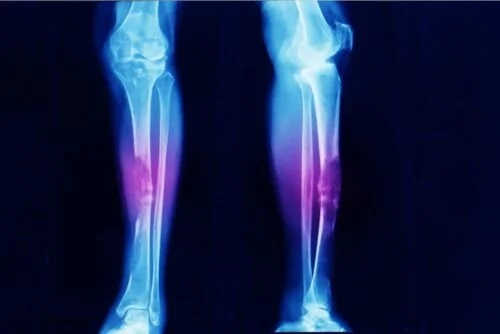

- Osteosarcomul, după cum indică și numele său, este cancerul osos.

Sarcoamele nu sunt comune. De fapt, diverse studii indică faptul că osteosarcomul (o tumoare a scheletului) reprezintă doar 0,2% din toate cazurile de cancer malign. Aceasta înseamnă că există o incidență de aproximativ 3 cazuri la 1 milion de oameni în fiecare an.